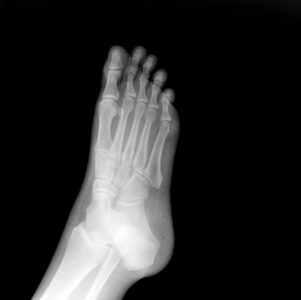

What Are Some Rare Foot And Ankle Problems?